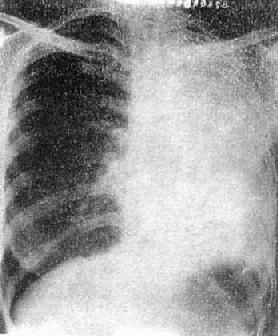

2)右肺中叶不张:较为常见,后前位表现为右肺下野内侧靠心右缘现上界清楚下界模糊的片状致密影,心右缘不能分辨(图3-1-9)。侧位上表现为自肺门向前下方倾斜的带状或尖端指向肺门的三角形致密影(图3-1-9)。上、下叶可有代偿性肺气肿。

图3-1-9 右肺中叶肺不张(正、侧位)